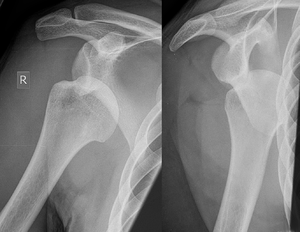

| Anterior shoulder dislocation on X-ray with a large Hill–Sachs lesion | |

A Hill–Sachs lesion, or Hill–Sachs fracture, is a cortical depression in the posterolateral head of the humerus. It results from forceful impaction of the humeral head against the anteroinferior glenoid rim when the shoulder is dislocated anteriorly.